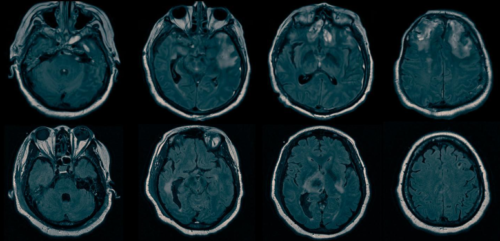

Patients with brain injury who are unresponsive to commands may perform cognitive tasks that are detected on functional magnetic resonance imaging (fMRI) and electroencephalography (EEG). This phenomenon, known as cognitive motor dissociation, has not been systematically studied in a large cohort of persons with disorders of consciousness.

In this prospective cohort study conducted at six international centers, we collected clinical, behavioral, and task-based fMRI and EEG data from a convenience sample of 353 adults with disorders of consciousness. We assessed the response to commands on task-based fMRI or EEG in participants without an observable response to verbal commands (i.e., those with a behavioral diagnosis of coma, vegetative state, or minimally conscious state–minus) and in participants with an observable response to verbal commands. The presence or absence of an observable response to commands was assessed with the use of the Coma Recovery Scale–Revised (CRS-R).

Data from fMRI only or EEG only were available for 65% of the participants, and data from both fMRI and EEG were available for 35%. The median age of the participants was 37.9 years, the median time between brain injury and assessment with the CRS-R was 7.9 months (25% of the participants were assessed with the CRS-R within 28 days after injury), and brain trauma was an etiologic factor in 50%. We detected cognitive motor dissociation in 60 of the 241 participants (25%) without an observable response to commands, of whom 11 had been assessed with the use of fMRI only, 13 with the use of EEG only, and 36 with the use of both techniques. Cognitive motor dissociation was associated with younger age, longer time since injury, and brain trauma as an etiologic factor. In contrast, responses on task-based fMRI or EEG occurred in 43 of 112 participants (38%) with an observable response to verbal commands.